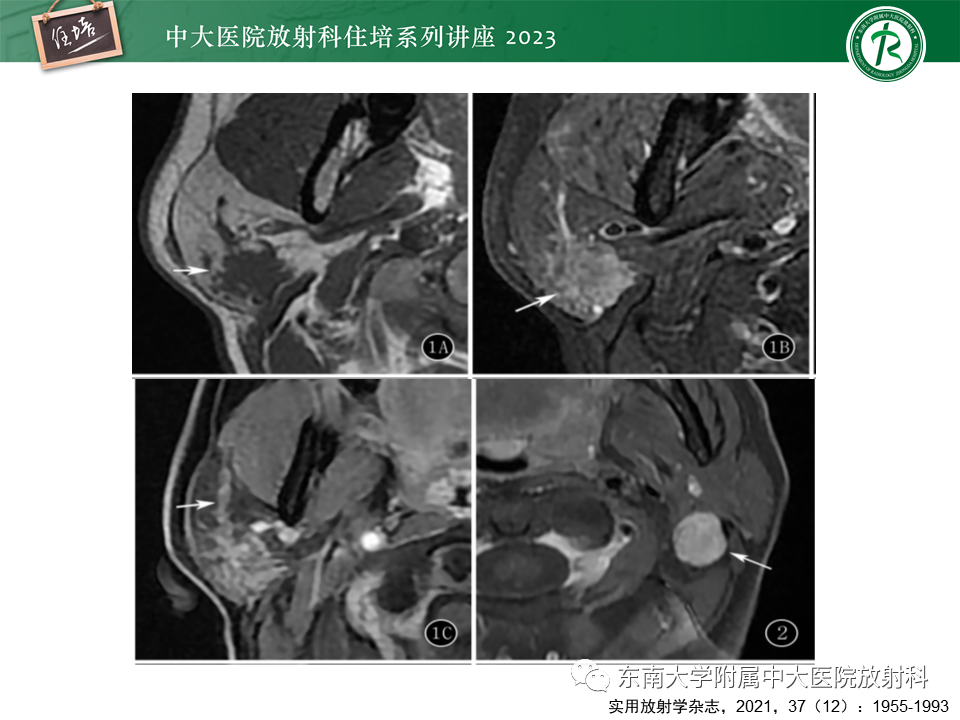

腮腺病变影像表现及诊断思路